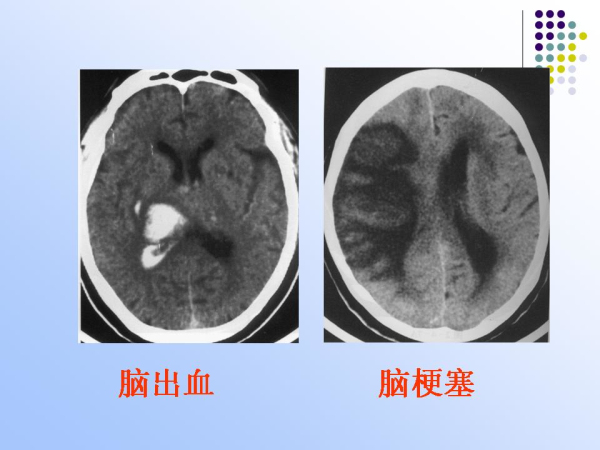

【治疗脑血管病的新技术:血管内介入治疗】—神经内科脑卒中筛查与防治办公室

神经内科

脑卒中筛查与防治办公室